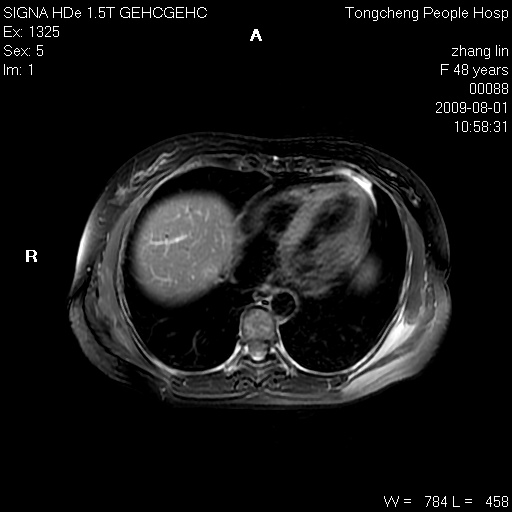

女,48岁。健康体检,彩超发现右肾占位性病变。平素健康。

临床诊断:右肾占位性病变,性质待定(囊肿?肿瘤?)。

上中腹部mr平扫+增强扫描,图像如下:

右肾上极见一类圆形病灶,t1wi呈等信号t2wi呈等高混杂信号,三期增强无强化,边界清---考虑囊肿出血。

同反相位均表现为等信号,病变无强化,考虑含蛋白的囊肿可能,弥散加权相或许有些帮助,

慢性胆囊炎